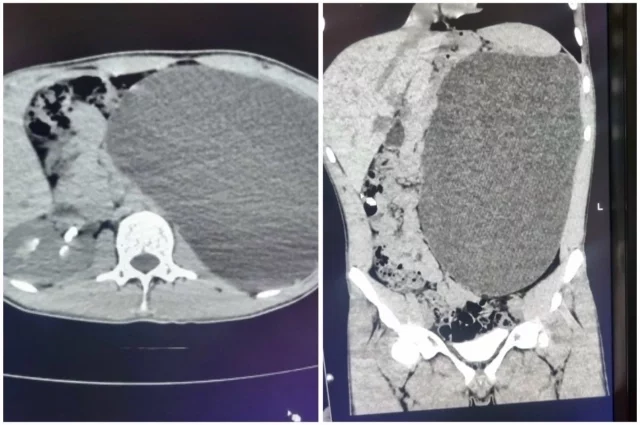

Хирурги-онкологи Центра Мешалкина в Новосибирске сохранили у пациентки единственную почку, удалив крупную злокачественную опухоль, сообщили в пресс-службе Центра.

В Центр Мешалкина 69-летнюю женщину направили из Алтайского края. У пациентки ряд заболеваний сердечно-сосудистой системы, а единственная почка была поражена опухолью. Вторую почку удалили 20 лет назад, также из-за онкологии.

Опухоль оказалась большой и сложно располагалась в почке. Кроме того, у пациентки был спаечный процесс и повышенная масса тела. В других медицинских учреждениях не взялись бы сохранить орган при операции. Однако онкологи Центра Мешалкина спланировали лапароскопическую операцию с риском потери почки всего в 20%.

Врачей тревожило, сможет ли единственная почка, ещё и уменьшившись на 5 см, восстановить функции и обеспечивать организм. Несмотря на риски, почка полностью восстановила показатели за 3 дня и соответствует уровню здорового человека.